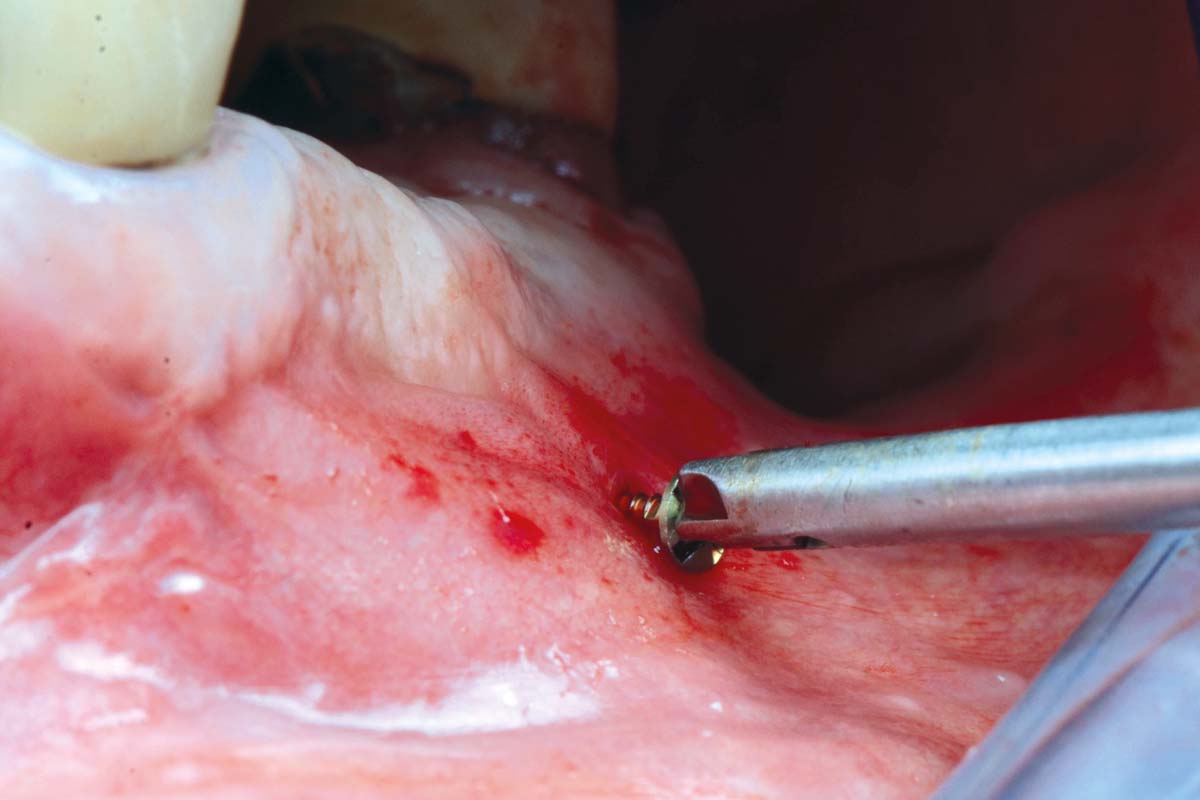

botiss maxgraft® bonebuilder and vestibuloplasty with mucoderm® for ridge augmentation - Clinical case